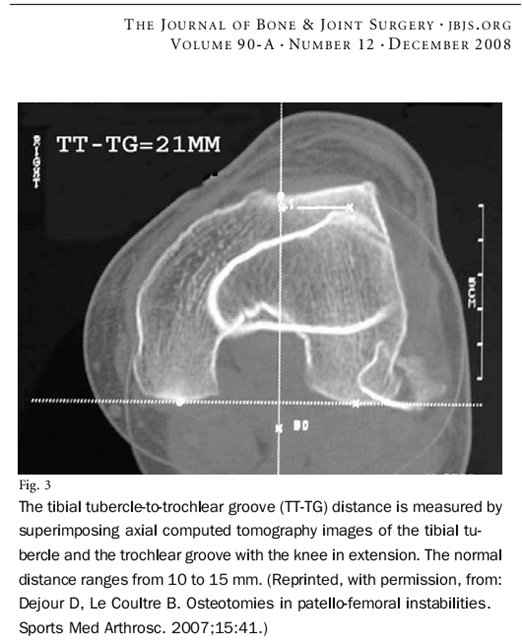

Среди показаний к дистальному реаттачтменту (медиализация, Элмсли-Трилат, Ру - Фридланд - Волков и др ) - как раз стоит пателла альта (которую лучше смотреть по индексу Блэкберн-Пил) и / или (именно и/или) нарушение этого индекса.

Ведь возможен вариант, когда пателлы альта не будет, а указанный индекс (TT-TG) - не норма.

Сравнение с Мерчант - имеется в виду качественное сравнение чувствительности и специфичности этого метода - интересный вопрос. Тем более что при нарушениях индексов на Мерчант и при нормальных TT-TG и Блэкберн рекомендуется реконструкция медиального аппарата.

В любом случае, JBJS пишет об этом индексе (TT-TG),значит мы его должны знать.